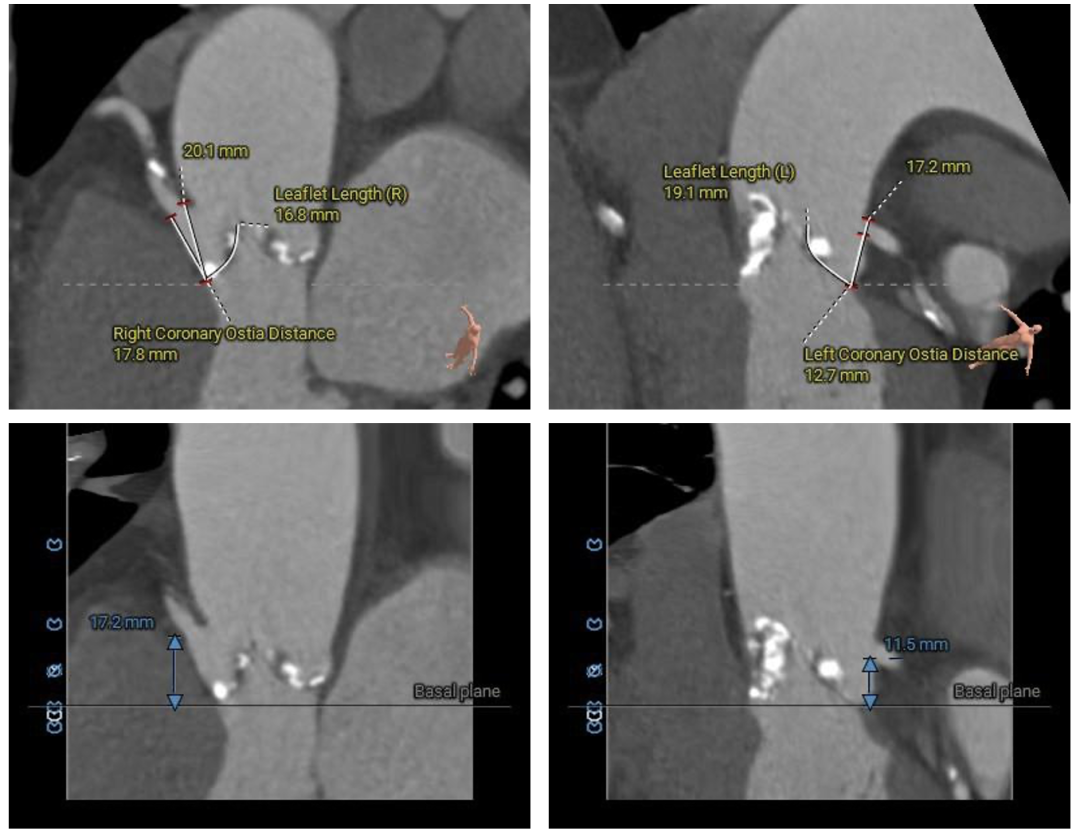

在完成术前CT扫描后发现,李阿姨入路腹主动脉严重扭曲、横位心、右冠窦无冠窦钙化融合且冠脉开口位置相对较低,左冠瓣叶冗长,术中冠脉闭塞风险高,这些不利因素均会明显增加手术的难度和风险。为此,医院迅速启动多学科协作机制,由医务处牵头,联合心血管科、麻醉科、重症医学科、血管外科、胸外科等专家团队展开会诊。经过反复讨论,专家团队最终决定采用国际先进的治疗方案一一经导管主动脉瓣置换术(TAVR)。这种微创手术无需开胸,只需通过血管穿刺即可完成瓣膜置换,极大降低了手术风险。为确保万无一失,心血管科团队还通过线上会议邀请国内知名专家对病例进行远程讨论,制定了精细化手术方案,包括入路解决方案、冠脉保护策略、术中应急措施以及术后康复计划。

▲术前CT评估

▲主动脉根部测量

▲冠脉测量

患者病理特点

1. 冠脉高风险:三窦三叶式主动脉瓣,右无之间钙化融合,钙化分布不均。右无融合脊会把瓣架往左冠脉开口方向推挤,并且左冠瓣叶相对冗长,大大增加了冠脉阻挡的风险。

2. 腹主入路折角:双侧入路血管走形良好,整体入路血管条件一般,腹主动脉可见扭曲,经过测量33cm可以正好通过迂曲部位,也提前备好45cm长鞘,以防血管损伤。

3. 瓣膜通过性:由于横位心及大弯侧有融合脊形成台阶,瓣膜输送器通过会受影响,预备同侧snare圈套,以防无法通过。